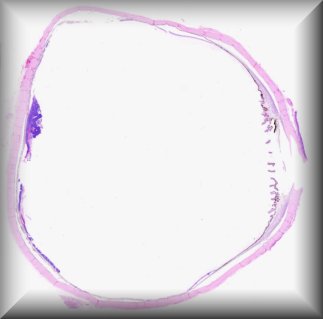

Luis Alfaro (Valencia): 53 year-old-man with a corneal transplant 3 years ago with poor evolution, who underwent retransplantation after being treated with amniotic membrane graft. |